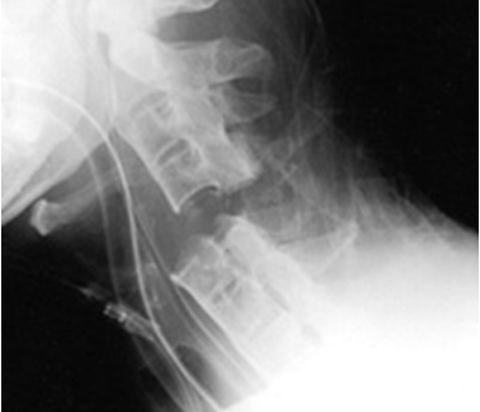

Learn MoreSpinal Trauma

Acute spinal injury management including spinal cord injury management both acutely and in the longer term. There are some complimentary sessions in the rehabilitation module.

Learn MoreTraumatic Spinal Injury

This module includes sessions on acute and longer term spinal injury including spinal cord injury management